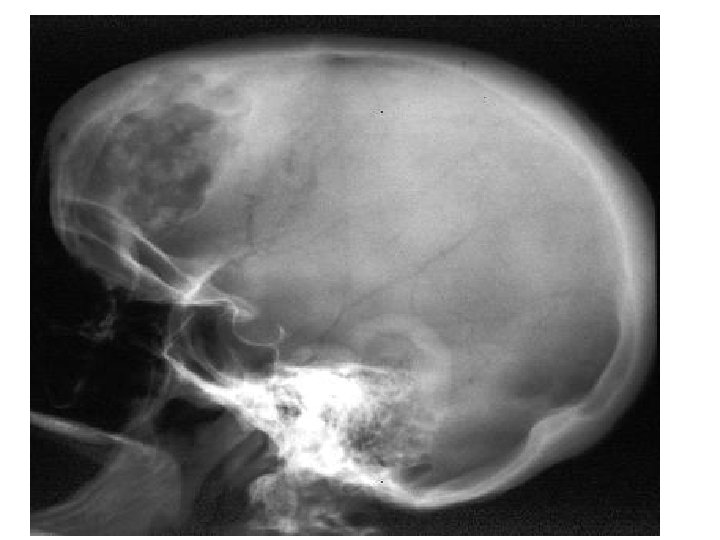

The Skull: • 8 bones in cranium • 13 Facial bones • 1 mandible Cranium: • encases brain • attachments for muscles • sinuses

Sinuses: · Hollow portions of bones surrounding the nasal cavity · Fill up with fluid to cause sinus pressure and headaches! Figure 5. 10 Copyright © 2003 Pearson Education, Inc. publishing as Benjamin Cummings Slide